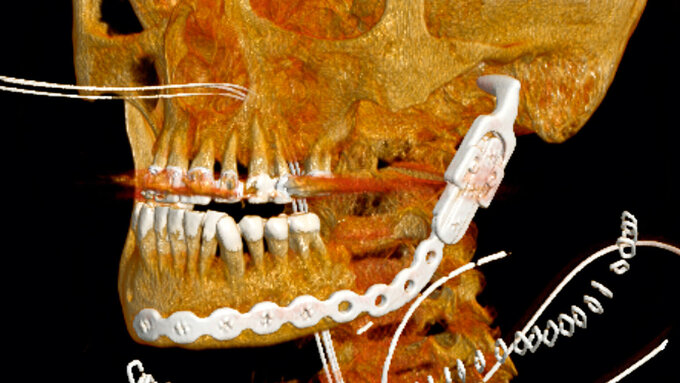

Radiologisch ließ sich eine ausgedehnte Knochendestruktion mit Sequesterbildung und Periostreaktion im vierten Quadranten nachweisen (Abbildung 3). Gemeinsam mit dem Patienten und insbesondere unter Berücksichtigung seiner extremen psychischen Belastung wurde anschließend die Entscheidung zur Dekortikation mit dem Versuch des Erhalts der Unterkieferkontinuität getroffen, wobei bei dem ausgeprägten klinischen Bild von ärztlicher Seite eine Kontinuitätsresektion unter Erhalt des Nervus alveolaris inferior in Kombination mit einer mikrovaskulären Rekonstruktion empfohlen wurde.

Die Operation konnte am Folgetag komplikationslos in Intubationsnarkose durchgeführt werden. Bei ausreichender Reststabilität des Unterkiefers wurde auf eine osteosynthetische Versorgung verzichtet (Abbildung 4). Die histopathologische Nachuntersuchung der intraoperativ gesammelten Knochenproben bestätigte die Verdachtsdiagnose einer sekundär chronischen Osteomyelitis. Es zeigten sich eine chronisch granulierende Entzündung der Schleimhaut sowie eine floride granulozytäre Infiltration der Markräume des erfassten kompakten Knochengewebes.